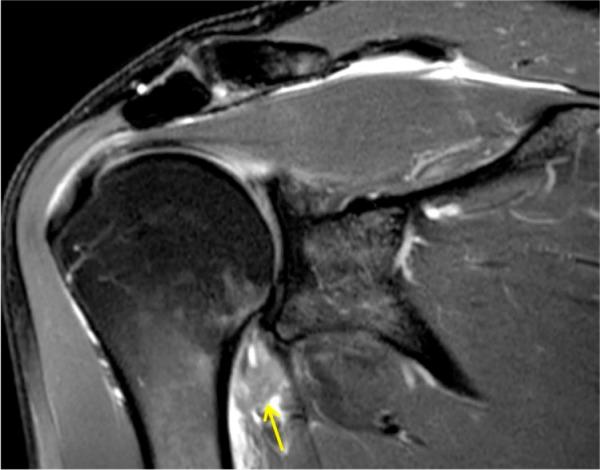

肩周炎关节腔扩张术的适应证

Indications for hydrodilatation for frozen shoulder.

肩周炎在以中年在职患者为主的人群中会导致严重的功能障碍和疼痛。肩周炎目前仍未得到充分了解。现有文献有限,且常常存在偏差。一种能减轻疼痛并恢复功能的快速、非手术且经济高效的治疗方法是一个有吸引力的选择。液压扩张术是二级医疗中肩周炎潜在的一线治疗方法。引用本文:2017;2:462 - 468。DOI:10.1302/2058 - 5241.2.160061。